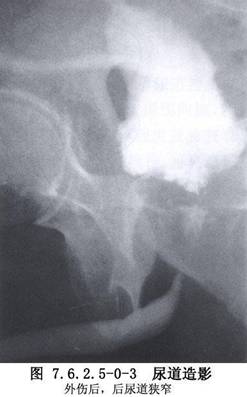

男性尿道狭窄是泌尿外科常见病,按其病因可分为先天性、炎症性和外伤性3类。先天性尿道狭窄较少见,如先天性尿道外口狭窄、尿道瓣膜、精阜肥大、尿道管腔缩窄等。炎症性尿道狭窄由特异性或非特异性尿道感染所致。特异性感染中,以淋病性尿道狭窄较常见;非特异性感染中,因反复包皮、阴茎头炎症所致的尿道外口及阴茎部尿道狭窄常见,因留置导尿管不当所致的炎症性尿道狭窄已引起广泛重视,这类狭窄多见于海绵体部尿道,范围较广;外伤性尿道狭窄(traumatic urethral stricture)是最常见的后天性尿道狭窄,狭窄部位依损伤部位而定,会阴跨骑伤所致者多在球部尿道。骨盆骨折所致者,位于膜部或前列腺尖端尿道,一般狭窄段不长,但瘢痕较坚硬(图7.6.2.5-0-1~7.6.2.5-0-3)。